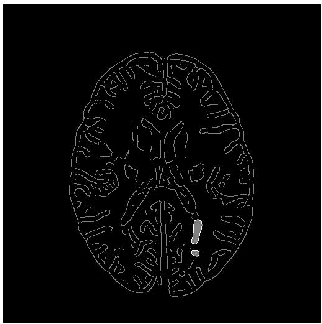

Abstract:Magnetic resonance images (MRI) play an important role in supporting and substituting clinical information in the diagnosis of multiple sclerosis (MS) disease by presenting lesion in brain MR images. In this paper, an algorithm for MS lesion segmentation from Brain MR Images has been presented. We revisit the modification of properties of fuzzy -c means algorithms and the canny edge detection. By changing and reformed fuzzy c-means clustering algorithms, and applying canny contraction principle, a relationship between MS lesions and edge detection is established. For the special case of FCM, we derive a sufficient condition and clustering parameters, allowing identification of them as (local) minima of the objective function.